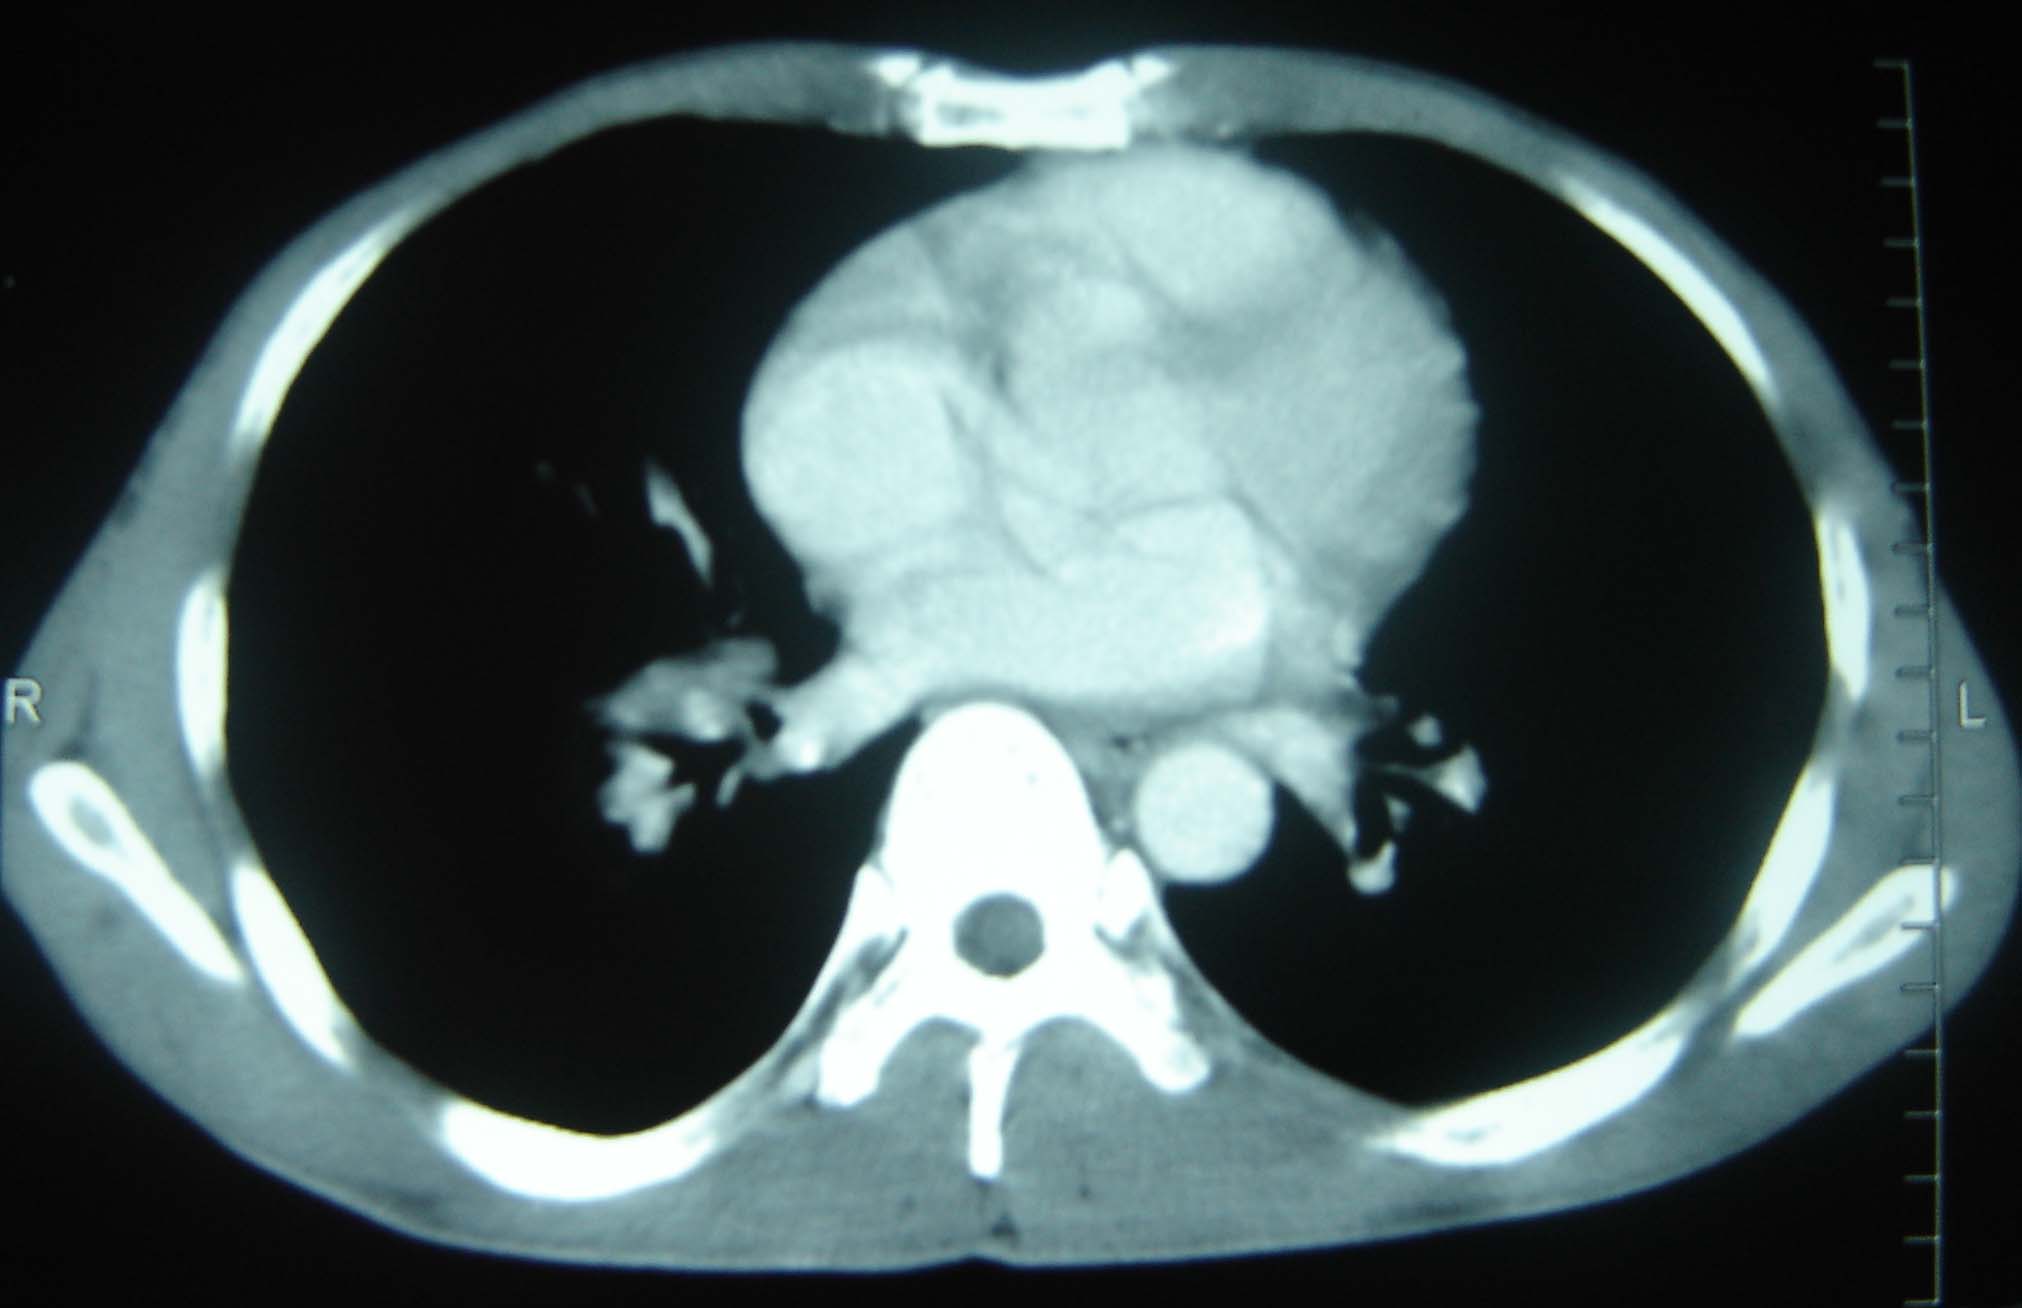

标题: CT25321:两肺多发结节 请会诊 [打印本页]

标题: CT25321:两肺多发结节 请会诊

男 、43岁,咳嗽胸痛,装修工,平时接触粉尘较多,有吸烟史10多年,纤维支气管镜检查未发现异常,胃镜、腹部b超检查亦未发现异常,颈部淋巴结活检未发现肿瘤细胞。

不能排除转移,如果不能找到原发灶,只有短期随访。

结节病?转移瘤?

1)考虑双肺及胸膜多发性转移瘤。2)肺气肿。